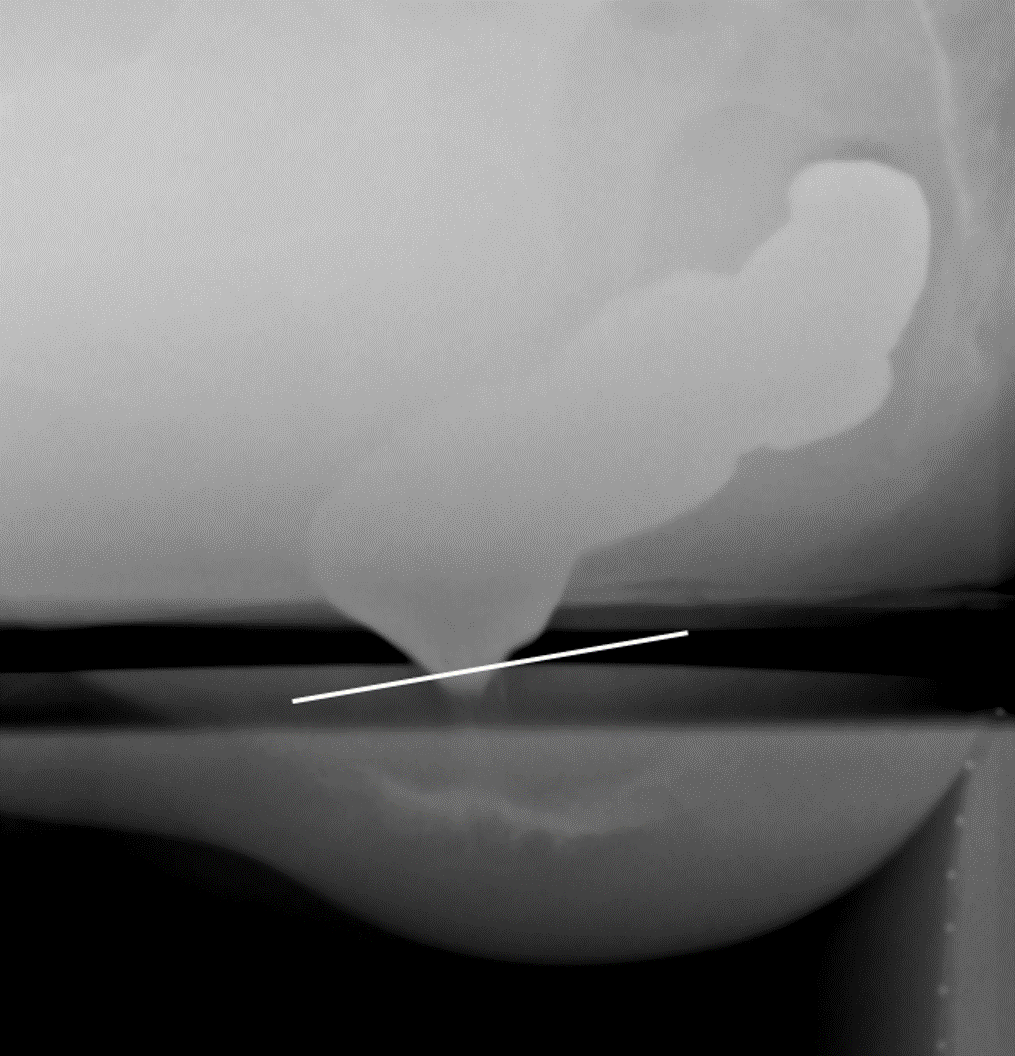

- With the patient seated on the defecography chair, obtain a scout image of the rectum and pelvis.

(key image 1). Be sure to include:

- the sacrum posteriorly

- the pubic symphysis anteriorly

- approximately 5cm below the skin surface of the perineum

- This extra room inferiorly will able you to view any prolapse that may occur without having to move the fluoro machine.

- the centimeter marker on the commode

- the barium-filled small bowel superiorly

- After obtaining the scout image, lock the fluoro tower in place.

- Do not move the tower after you have taken the scout image.

- This will ensure that you are able to measure descent of the pelvic floor appropriately.